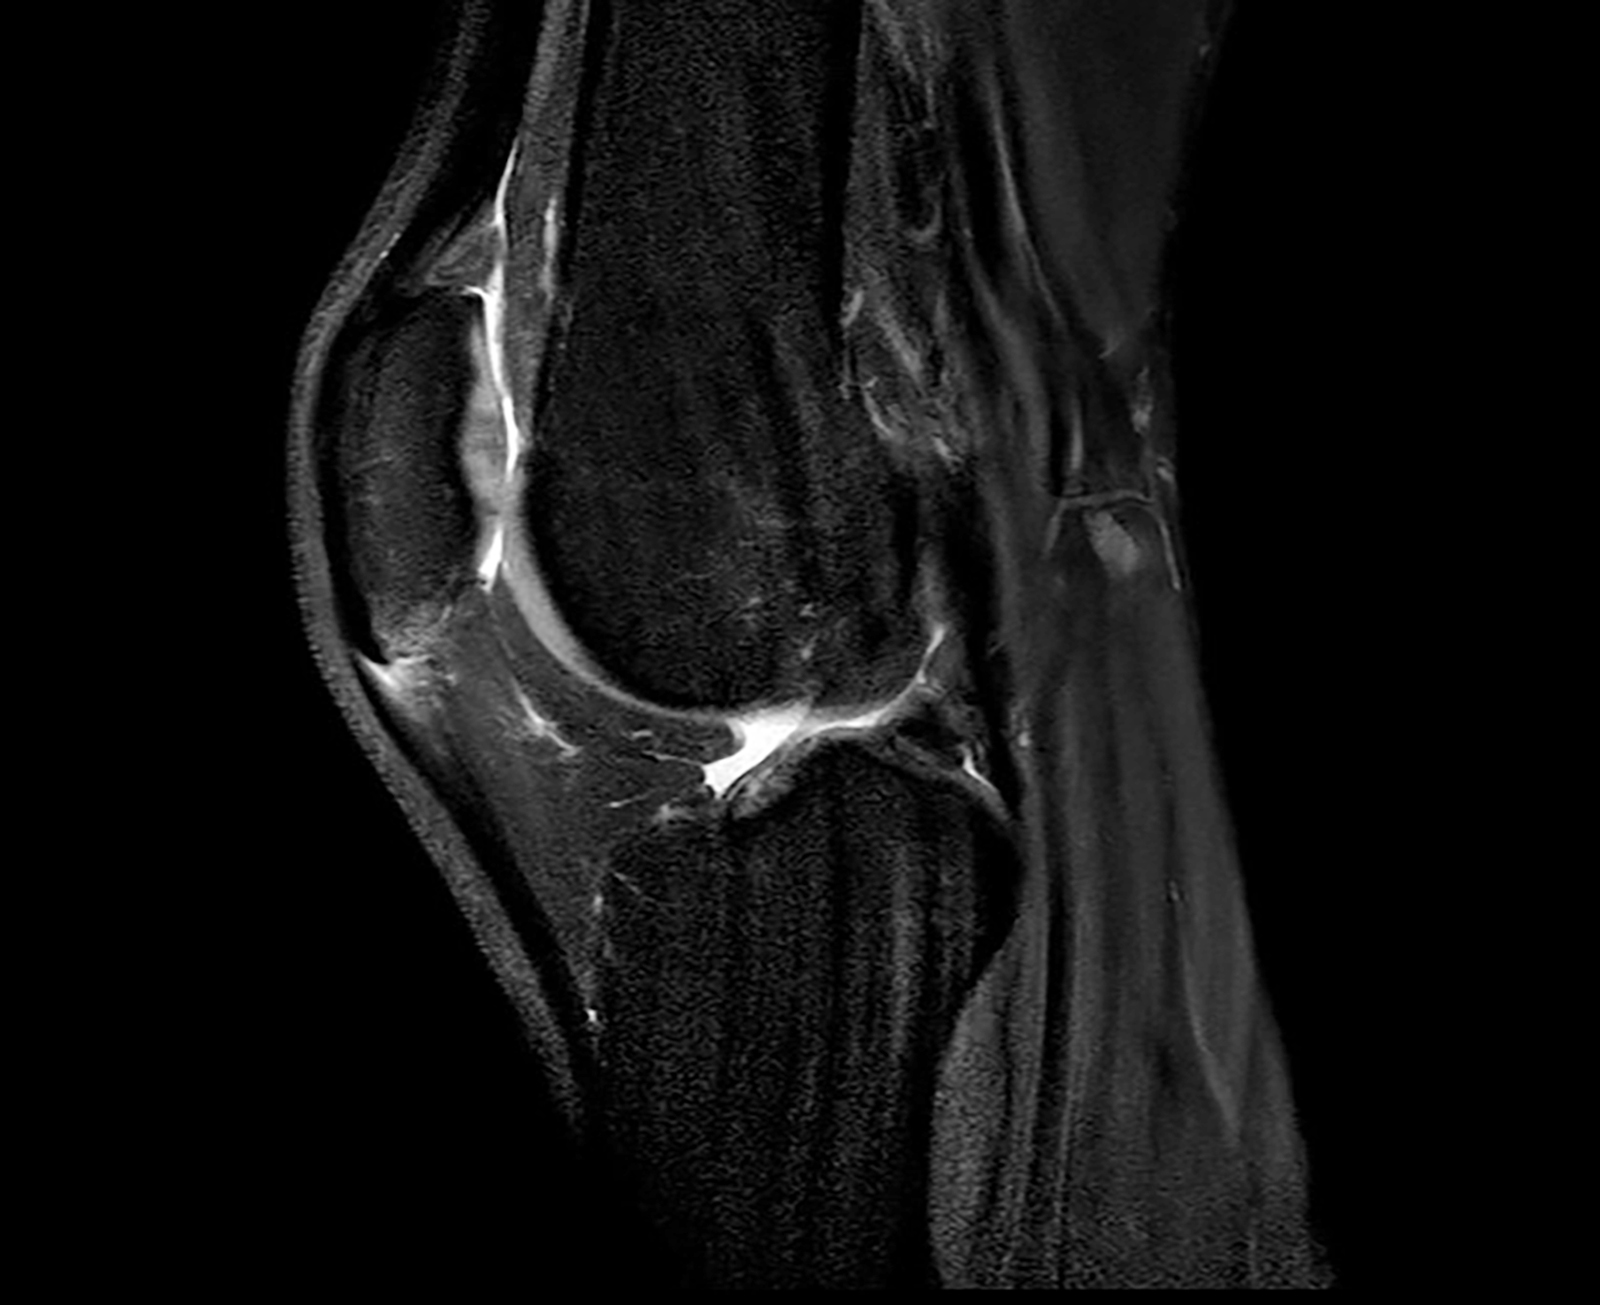

Im Mittelpunkt steht bei der Tendinopathie ein ungünstiges Verhältnis zwischen chronischer Belastung und Belastbarkeit der Sehne durch vermehrte Bildung von Typ-III-Kollagen. Prinzipiell wird Typ-III-Kollagen zwar in frühen Heilungsphasen vermehrt gebildet, aber später auch wieder durch den stabileren Kollagentyp I ersetzt. Kurzfristig ist eine gewisse Zunahme von Typ III daher Teil des natürlichen Reparationsprozesses. Bleibt jedoch ein hoher Typ-III-Anteil im Sehnengewebe bestehen, führt das zu einer qualitativ minderwertigen Gewebestruktur, da Typ III mechanisch weniger belastbar ist als Typ I – das ist das narbig veränderte Sehnenareal, das im Ultraschall als hypoechogene Zone erscheint (Abb. 1). Im weiteren Verlauf erfolgt das remodeling der Sehne um dieses tendinopathische Areal herum und es kommt zur Größenzunahme des Gewebes [2, 4, 9]. Um diesen chronischen Prozess der Tendinopathie zu durchbrechen und eine strukturelle Heilung zu ermöglichen, kann das erwähnte Verfahren als eine Form der perkutanen ultraschallgestützten Tenotomie angewendet werden. Das Unternehmen TENEX (Tenex Health Inc.) hat ein eigenes Gerät entwickelt, das krankhaftes Sehnengewebe durch eine Ultraschallsonde mit Saug- und Spülsystem entfernen kann. Dabei kommt ein handgeführtes Instrument mit einer doppellumigen Ultraschall-Vibrationsnadel zum Einsatz, das über eine Stichinzision unter sonografischer Sicht in das tendinopathische Areal eingebracht werden kann (Abb. 2). Der postulierte Wirkmechanismus basiert auf der Phakoemulsifikation (Zertrümmerung) von nekrotischem Sehnen- und Narbengewebe, wobei gesundes Gewebe aufgrund anderer biomechanischer Eigenschaften intakt bleibt – analog zur Behandlung des Grauen Star am Auge. In Folge kommt es zu einer gezielten Auslösung einer Entzündungsreaktion, um Reparaturprozesse anzukurbeln, sodass die Sehne wieder im gesunden heilen kann. Man drückt quasi den reset button der Sehnenheilung [3, 6, 8].

Das ganze System ist dann 2018 zusammengebrochen, nachdem diese Reizung / Symptomatik an der Spitze so sehr zugenommen hatte, dass klar war, dass das behandlungsbedürftig war. Wir hatten damals im 11/ 2018 ein MRT gemacht und festgestellt, dass die Entzündung an der Patellaspitze so groß wie noch nie war. Daraufhin gab es eine einige Wochen Pause und ACP Therapie. Nach der Therapie habe ich fast das restliche Jahr mich einem Return-To-Sports-Programm gewidmet, um Schritt für Schritt wieder an die Belastung herangeführt zu werden. Das hatte leider nicht den erhofften langfristigen Erfolg gebracht, sondern es ist in den Folgejahren immer wieder unterschiedlich stark aufgeflammt und hat mich in meiner Sportlichkeit als Hochspringer gebremst.

Ende 2023 war ich zuversichtlich das Problem durch gezieltes Training der Sehne kontrollieren zu können. Ich besuchte die Charité in Berlin, um dort einen exakt für meine Sehne angepassten Trainingsplan nach der Berliner Methode zu ermitteln und umzusetzen. Leider musste ich in der folgenden Hallensaison 2024 feststellen, dass das nicht ausreichend war und die Sehne doch medizinische Aufmerksamkeit braucht. Das Sehnentraining war zu diesem Zeitpunkt bereits zermürbend und schwer aufrecht zu erhalten. Ein Angebot der Praxis im September 2022, noch einmal den Zustand zu überprüfen und gegebenenfalls mit fokussierter Stoßwelle oder ACP in der Off-Season zu arbeiten, hatte ich nicht wahrgenommen, da ich fester Überzeugung war, an dem Punkt das Problem durch korrektes Training und Pflege der Sehne weiter im Griff haben zu können oder abzuschließen. Die Saison 2023 war eben weitestgehend beschwerdefrei! Nachdem ich mir einen Längsriss in einem Wettkampfsprung im Februar 2024 an der Sehne hinzugezogen hatte, war ich wieder in medizinischer Betreuung und wir haben die Sehne erneut unter die Lupe genommen haben. Dabei mussten wir feststellen, dass die Tendinopathie nach wie vor vorhanden war und zugenommen hatte. Das war bitter zu dem Zeitpunkt, da ich mich schon in der unmittelbaren Vorbereitung vor den Olympischen Spielen 2024 befand. Der Längsriss konnte sehr erfolgreich mit ACP therapiert werden und war dann auch in kürzester Zeit ausgeheilt. Allerdings, kurz vor Saisonbeginn 2024, hatte sich die Symptomatik an der Spitze erneut so sehr zugespitzt, dass es mir nicht mehr möglich war, normal zu rennen, geschweige denn zu springen.

Als ich Ende April mit extremen Beschwerden an der Patellaspitze aus einem Trainingslager zurückkam und direkt montags zur Untersuchung in die Praxis nach dem MRT kam, wurde ich über die TENEX-OP-Methode informiert, welche auch als vorletzte Eskalationsstufe zur Behandlung von Tendopathien gilt. Das war dann die Last-Minute-Chance, 100 Tage vor Paris, um die Möglichkeit zu kriegen, an den Olympischen Spielen teilzunehmen, dachte ich mir. Qualifiziert war ich schon, vor allem durch meine sehr starke Vorjahresleistung und bis zur Verletzung erfolgreiche Hallensaison. Grundsätzlich war ich auch in einem sehr guten Trainingszustand – eben bis auf die Patellasehne. Nach kurzer Bedenkzeit habe ich innerhalb von einer Woche mich für den minimal invasiven Eingriff entschieden. In der ersten Maiwoche sollte die OP durchführt werden, um noch so viel Zeit wie möglich vor den Olympischen Sommerspielen Anfang August zur Regeneration zu haben. Ich kann mich noch gut erinnern, als alle Orthopäden der Praxis versammelt in einem Raum waren und mit mir und meinem Trainer gemeinsam diese Option diskutiert haben. Ich hatte keine Zweifel und war fest überzeugt, dass das jetzt der Weg ist, den ich einschlagen muss, um eine Chance zu bekommen! Ich war dankbar für die weiteren Optionen und neuen möglichen Lösungen, die mir hier aufgezeigt wurden. Vor allem bei so einer langjährigen Symptomatik habe ich schon von vielen Ansätzen gehört und viele auch ausprobiert. Ich weiß, dass es immer ein Risiko gibt und man in jede Therapie Zeit und Geduld investieren muss, um festzustellen, ob es für einen funktioniert oder nicht. Aber in diesem Fall gab es nicht mehr viel Zeit für Experimente.

In der Zwischenzeit konnte ich nach längerer Pause wieder umfangreicher trainieren. Die Patellasehne ist auch bei der letzten Bildgebung aus dem Januar deutlich besser als die letzte vor der OP, so das man nur von einer leichten Reizung sprechen kann. Sie war die meiste Zeit symptomfrei, allerdings ist das Problem nach wie vor noch nicht ganz aus der Welt. Sehnentraining und Pflege gehören weiterhin zu meinem Trainingsalltag. Mittlerweile auch für mehrere Sehnen an meinem Sprungbein, Plantar/ Achilles/ Patella. Sicherlich ist das langsam altersbedingt in meiner Sportart, was aber erst einmal nichts über die Leistungsfähigkeit aussagt, sondern nur weitere Anpassung des Trainings erfordert! Ich habe in der gesamten Zeit der Tendopathie beinahe jede Therapieform merhfach genutzt, Hyaluron, Traumeel, ACP, Milchsaure, Aktovegin, Blutegel, Röntgenreiz (3x!), Infrarot, f-ESWT, EPTe (Elektrolyse) und sicher habe ich sogar noch etwas vergessen. Ich würde die Entscheidung für die OP noch einmal treffen, allerdings mit ausreichend Zeit und Nachbereitung. Vielleicht kann man das TENEX sogar früher in Erwägung ziehen.